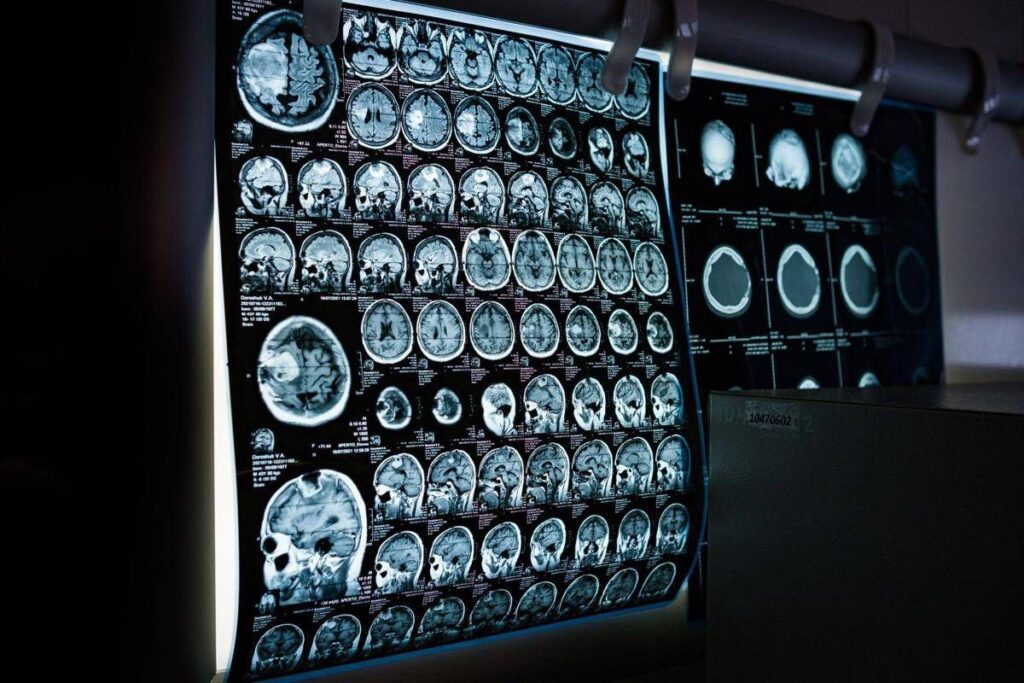

E’ il risultato dello studio condotto dai ricercatori della Texas A&M University (Naresh K. Vashisht College of Medicine) negli Stati Uniti. Lo spray contiene minuscole particelle biologiche note come vescicole extracellulari (Ev), che agiscono come veicoli di consegna con a bordo un potente carico genetico, i microRna. Le sostanze aggirano lo scudo protettivo del cervello e viaggiano direttamente nel tessuto cerebrale, dove vengono assorbite. Arrivati a destinazione nelle cellule immunitarie residenti nel cervello, i microRna ‘spengono’ i sistemi noti per essere responsabili dell’infiammazione cronica nel cervello che invecchia.Â

Per spiegare il senso di questo processo, gli scienziati invitano a immaginare il cervello come un motore ad alte prestazioni: nel corso dei decenni questo motore non solo si usura, ma inizia anche a surriscaldarsi. Piccoli ‘focolai’ di infiammazione covano nelle profondità del centro della memoria, creando una persistente nebbia mentale (brain fog) che rende più difficile pensare, formare nuovi ricordi o persino adattarsi a nuovi ambienti, aumentando al contempo il rischio di disturbi come il morbo di Alzheimer. Questo processo a lenta combustione viene chiamato neuroinfiammazione. E per decenni si è pensato che fosse il prezzo inevitabile dell’invecchiamento. Ma il nuovo studio, pubblicato sul ‘Journal of Extracellular Vesicles’, suggerisce che l’ondata infiammatoria potrebbe essere reversibile.Â

Il team guidato da Ashok Shetty, distinguished professor dell’ateneo e associate director dell’Istituto di medicina rigenerativa, insieme ai ricercatori senior Madhu Leelavathi Narayana e Maheedhar Kodali, ha sviluppato lo spray nasale e ha verificato che a livello cellulare il trattamento ha ricaricato i mitocondri neuronali, ovvero le centrali energetiche che si trovano all’interno delle cellule cerebrali. La terapia ha dissipato la nebbia mentale e ha anche migliorato fisicamente la capacità del cervello di elaborare e immagazzinare informazioni.Â